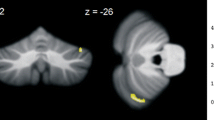

We found GM density excess (FDR p < 0.05) in regions I–IV of the cerebellar lobes bilaterally compared to controls (Table 1 and Fig. 1). We observed GM density reduction (FDR p < 0.05) in regions VI on the right and V–VI on the left (Table 1 and Fig. 1).

The GM density excess was found symmetrically in regions I–IV of the anterior cerebellar lobe. The subarea III, mainly lobule IV, is directly involved in upper limb motor control [20]. Gait and appendicular ataxia, dysarthria, as well as the control of tongue movements and orofacial muscles are directly related to the integrity of these regions [21].

We found GM density reduction mostly in areas VI of posterior cerebellar lobes bilaterally and V of anterior cerebellar lobe on the left. Both are part of the sensorimotor cerebellum and are directly involved in learning and cognitive processing [22]. These areas are also indirectly attached to the prefrontal cortex through the dentate-rubral-thalamic tract, and the ventral portion of the dentate nucleus is the interface between those two areas [20].